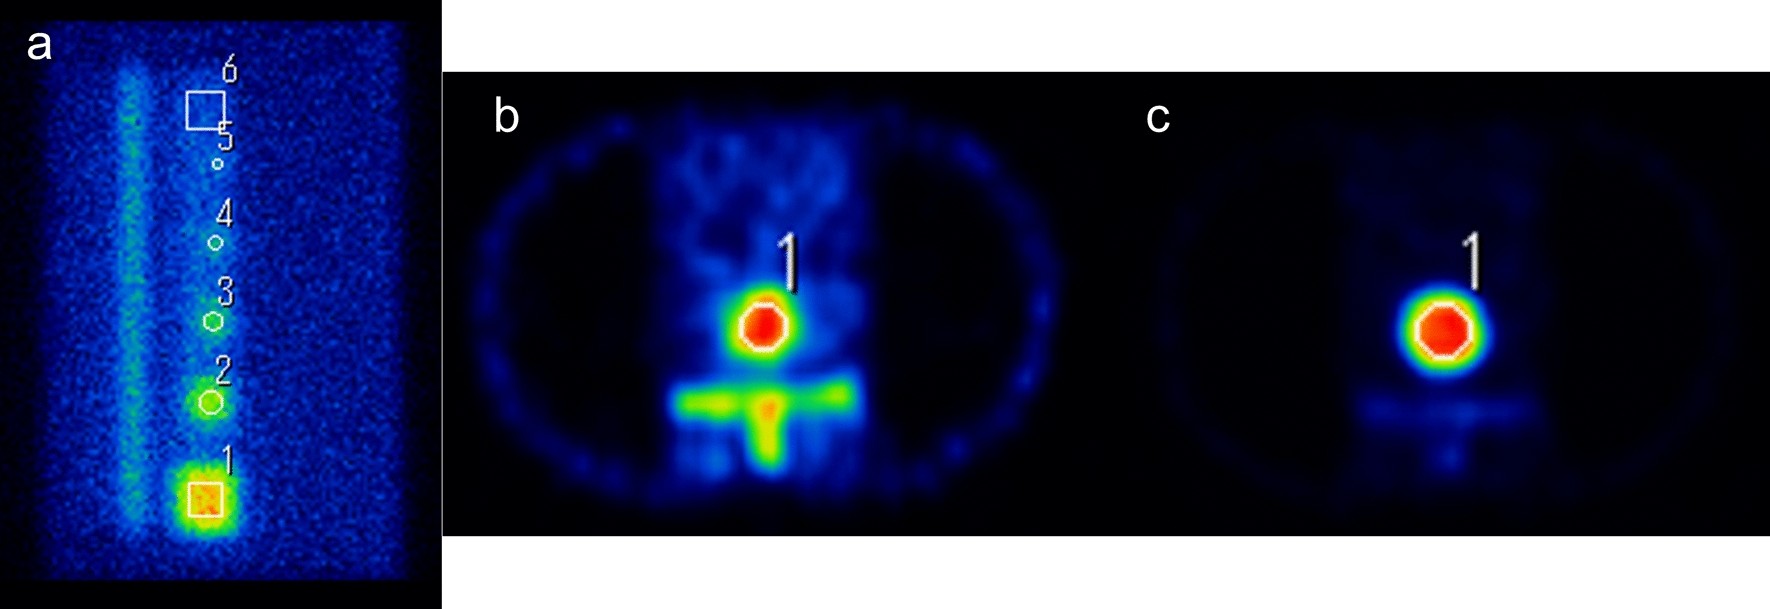

Figure 2

Planar and SPECT images calculating contrast to noise ratio (CNR) and the percent of the coefficient of variance (%CV). (a) Lateral view image with SwiftScan planar, transverse image of (b) tumor bone and (c) normal bone. Circle or rectangle ROI was set to each tumor and normal bones in planar and SPECT images using Prominence processor version 3.1 software (http://nm.jsrt.or.jp/blog.html) provided by Japanese Society of Radiological Technology’s subgroup Nuclear Medicine Section.